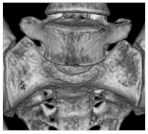

| I | Ia: Unilateral dysplastic transversal process > 19 mm Ib: Bilateral dysplastic transversal process > 19 mm | Ib![]() |

| II | IIa: Unilateral pseudarthrosis between transversal process and sacral bone IIb: Bilateral pseudarthrosis between transversal process and sacral bone | IIa![]() |

| III | IIIa: Unilateral bony union between transversal process and sacral bone IIIb: Bilateral bony union between transversal process and sacral bone | IIIb![]() |

| IV | Unilateral bony union contralateral pseudarthrosis between transversal process and sacral bone | IV![]() |